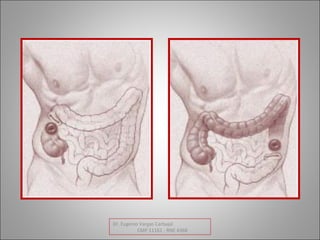

EN LA OBSTRUCCION SIMPLE EL ASA SE ENCUENTRA

BLOQUEADA EN UN SOLO LUGAR.

EN LA OBSTRUCCION EN ASA CERRADA EL ASA ESTA

BLOQUEADA EN DOS LUGARES.

OBSTRUCCION SIMPLE OBSTRUCCION EN ASA CERRADA